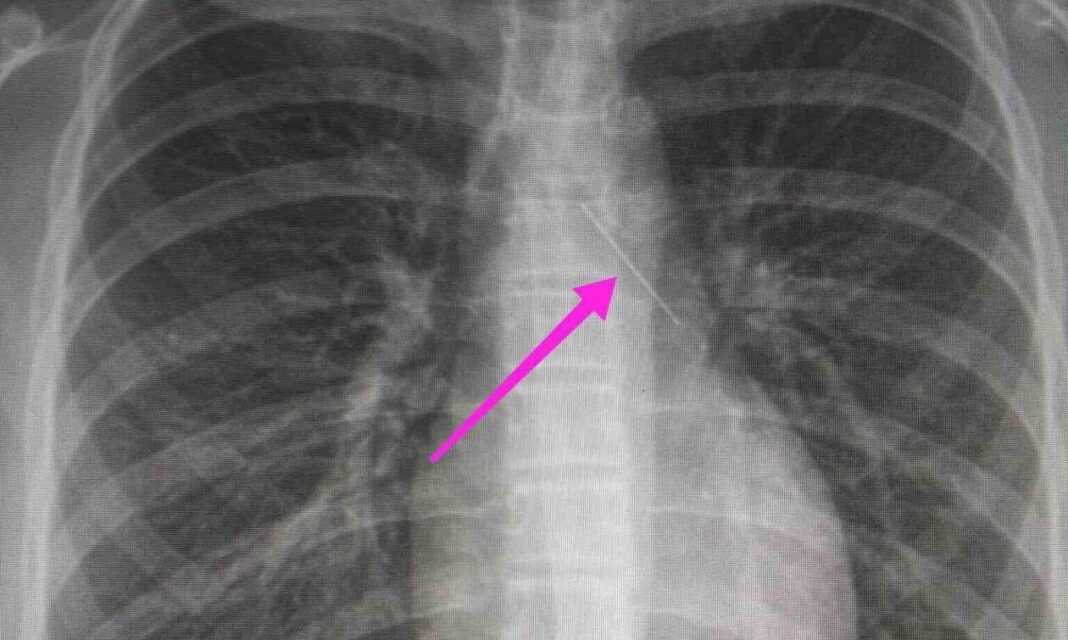

Σύμφωνα με την ιστοσελίδα thestival.gr, από την απεικονιστική διερεύνηση που πραγματοποιήθηκε με ακτινογραφία θώρακος αρχικά και ακολούθως με αξονική τομογραφία θώρακος, διαπιστώθηκε η ύπαρξη αιχμηρού μεταλλικού ξένου σώματος στην αναπνευστική οδό (αριστερός κύριος βρόγχος) και όχι στην πεπτική οδό, αναφέρει η ανακοίνωση του νοσοκομείου, στα μέσα κοινωνικής δικτύωσης.

«Χθες 30/1/2022 στις 16:00 στο Τ.Ε.Π. του ΓΝΘ Ιπποκράτειο, προσήλθε ανήλικη συνοδευόμενη από τους γονείς της, μετά από αναφερόμενη κατάποση ξένου σώματος (καρφίτσα). Από την απεικονιστική διερεύνηση που πραγματοποιήθηκε με ακτινογραφία θώρακος αρχικά και ακολούθως με αξονική τομογραφία θώρακος, διαπιστώθηκε η ύπαρξη αιχμηρού μεταλλικού ξένου σώματος στην αναπνευστική οδό (αριστερός κύριος βρόγχος) και όχι στην πεπτική οδό.